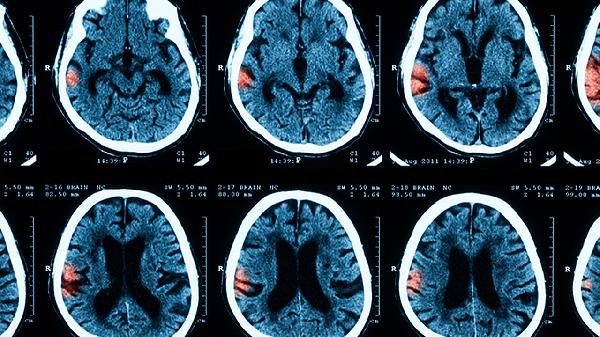

保持良好的卫生习惯,尤其是手部清洁,可以有效减少感染的风险。定期带孩子进行神经发育评估,并在必要时进行磁共振成像检查,以监测和预防潜在的健康问题。家长的细心观察和积极配合医疗建议是保障婴儿健康的重要因素。